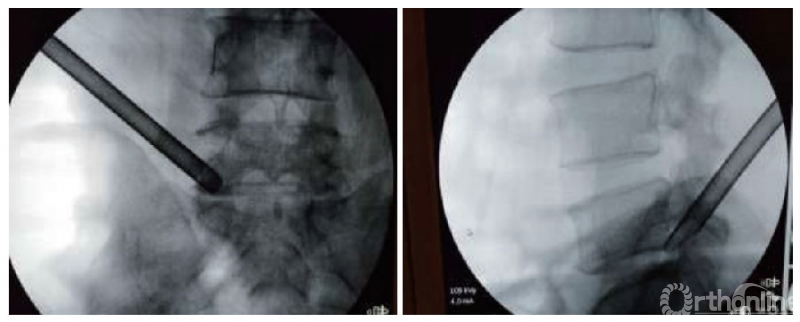

(3)放置工作套筒:穿刺尖刀切开皮肤0.8cm,采用穿刺针沿穿刺方向与身体平面夹角成25°-30°穿刺到S1上关节突顶点外缘,G型臂透视正侧位确定穿刺针指向椎间盘突出的靶点。拔出穿刺针的针芯,置入导针,拔出穿刺针,沿导针将TOMShidi针置入,拔出导针置入TOMShidi针内芯,用骨锤轻轻敲击TOMShidi针穿过关节突关节抵达椎间盘突出靶点。拔出TOMShidi针内芯,置入导针再取出TOMShidi针。沿导针依次用直径为4、6、7、8mm的骨钻逐级扩张椎间孔通道。沿导针放置扩张器和工作套筒,G型臂透视正侧位确定工作套筒位置位于腰椎间盘突出靶点(图1)。在穿刺及扩张通道过程中注意询问患者有无腰痛及下肢放射性疼痛,如果有疼痛则追加麻药。

图注:A组为伴有高髂嵴的L5/S1椎间盘突出症患者,采用侧方入路经皮椎间孔镜下椎间盘切除治疗。正、侧位透视显示工作套筒位于侧方入路经皮椎间孔镜下椎间盘切除术中高髂嵴腰椎间盘突出患者的靶点位置

图1|A组正、侧位透视图片